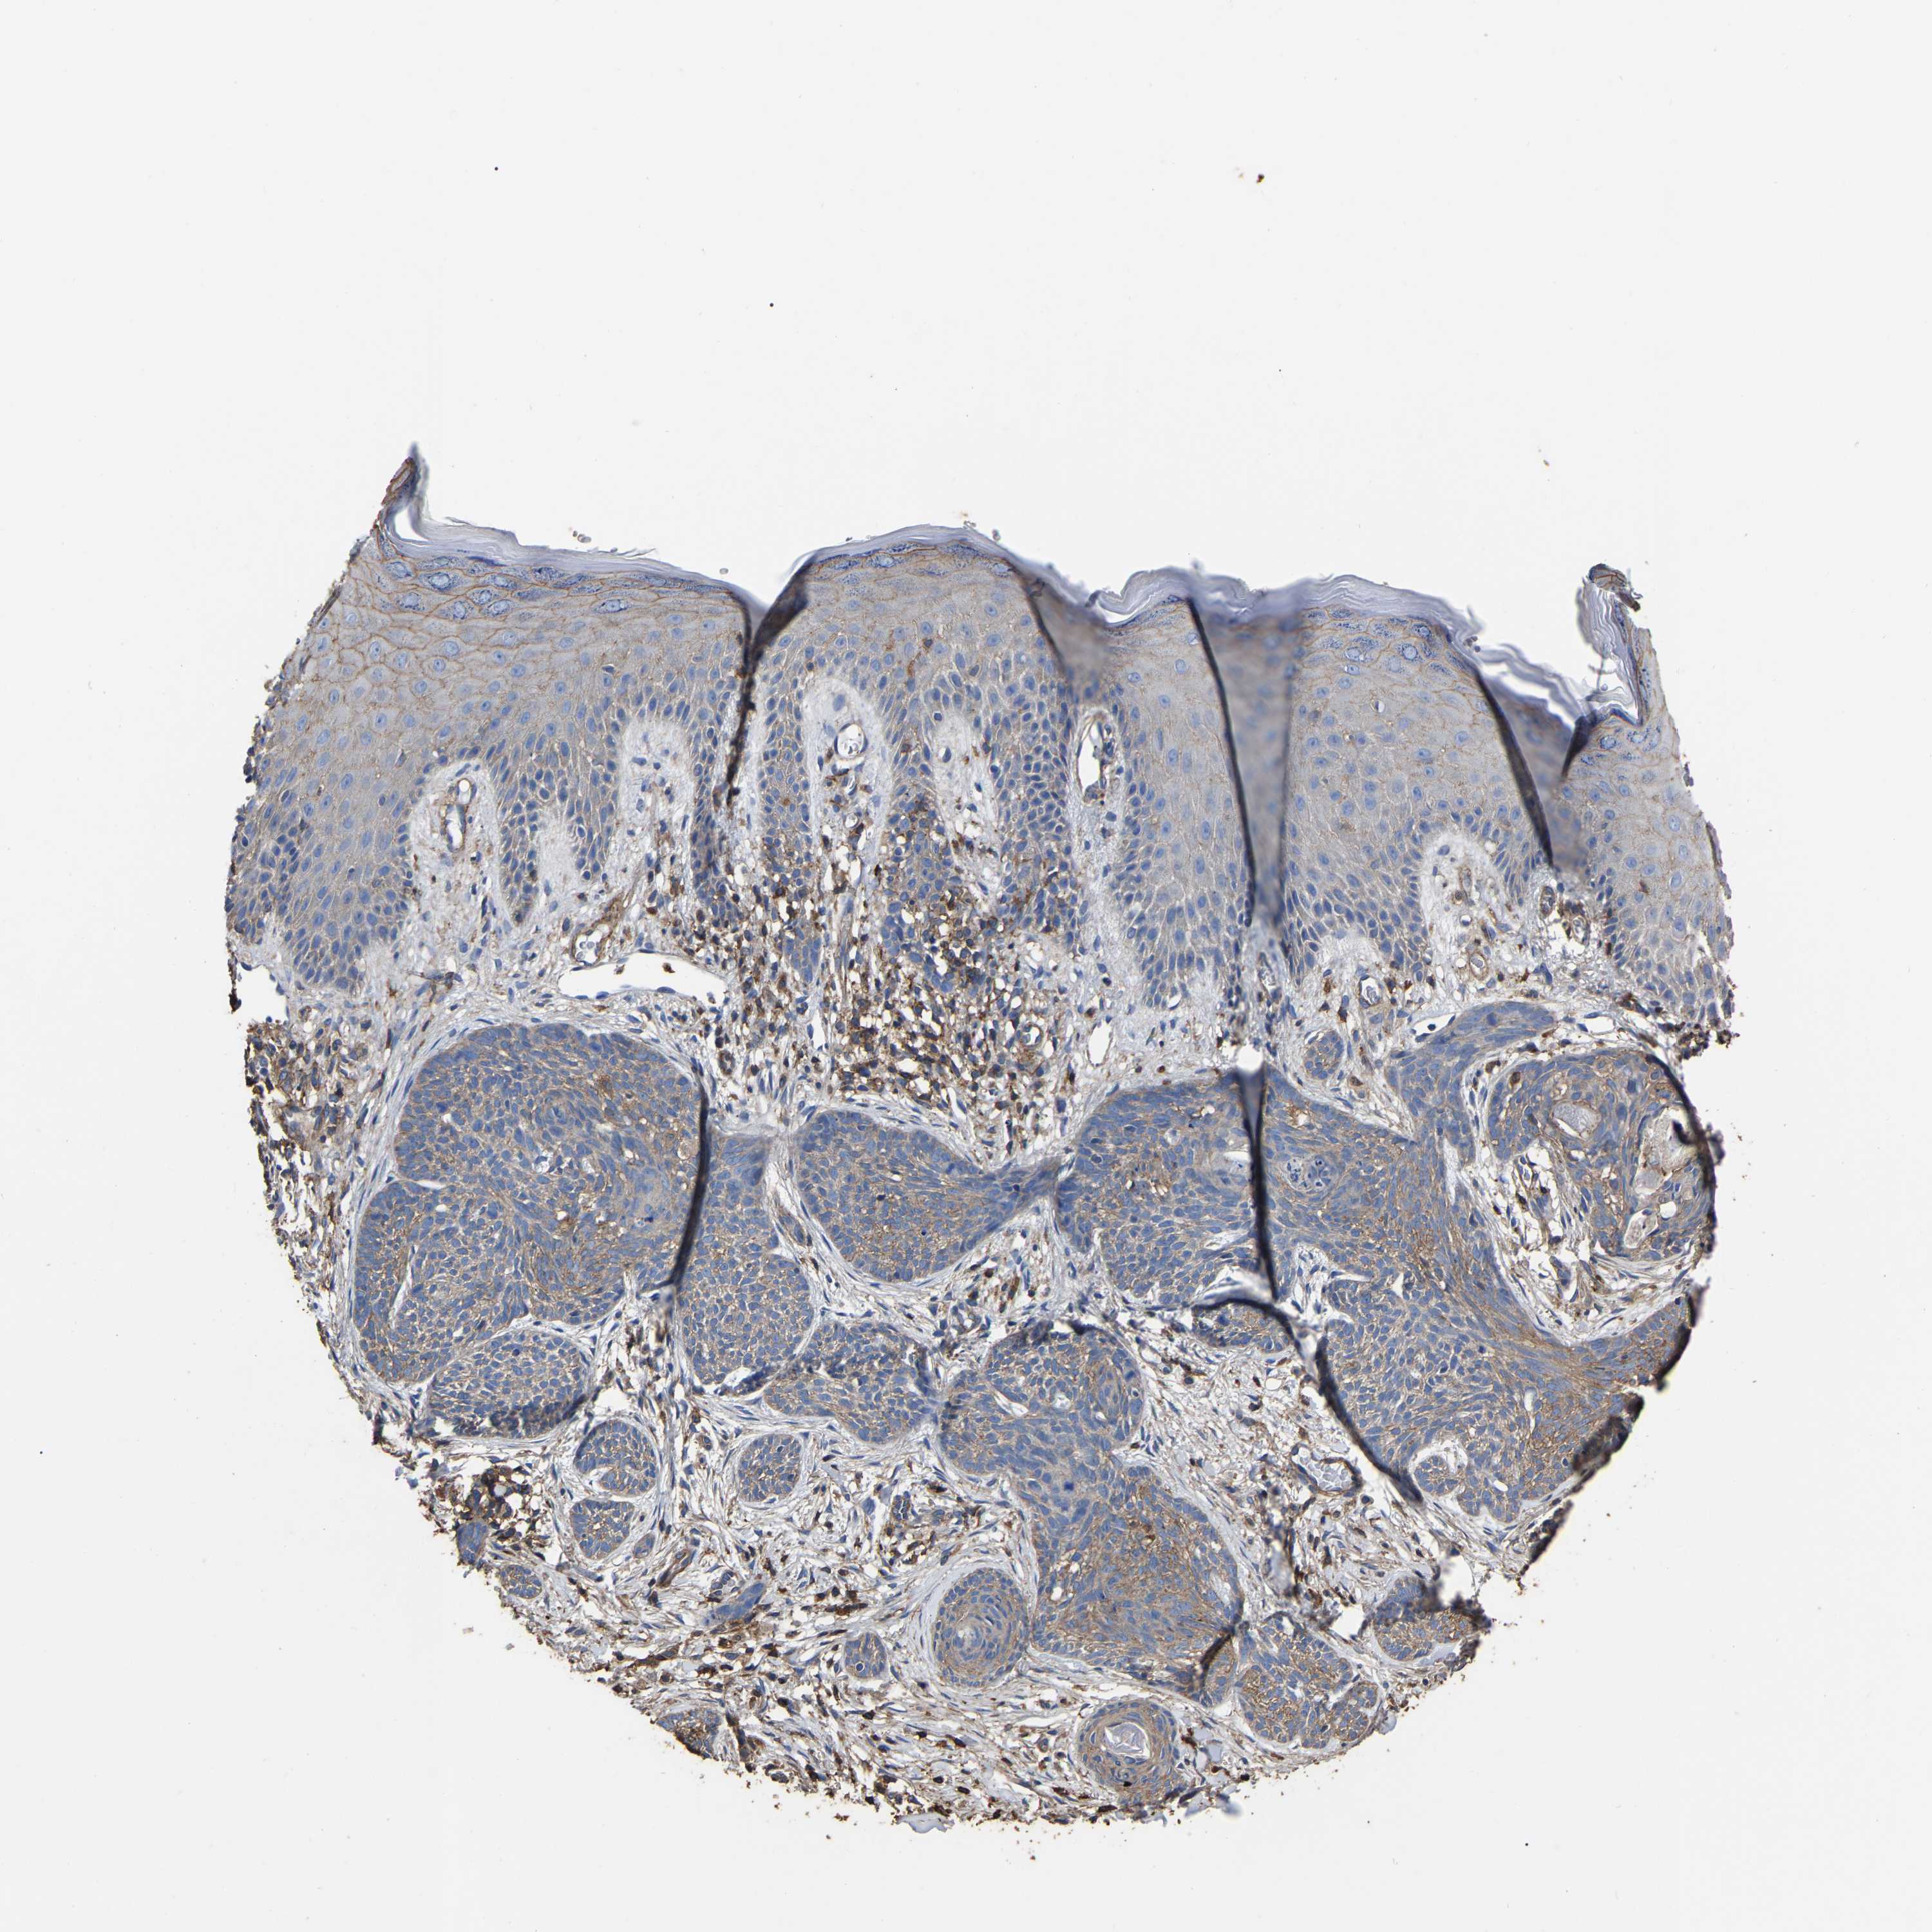

SKIN CANCER - Protein expressioni

A mouse-over function shows sample information and annotation data. Click on an image to view it in a full screen mode. Samples can be filtered based on level of antibody staining by selecting one or several of the following categories: high, medium, low and not detected. The assay and annotation is described here.

Antibody staining in the annotated cell types in the current human tissue is reported as not detected, low, medium, or high, based on conventional immunohistochemistry profiling in selected tissues. This score is based on the combination of the staining intensity and fraction of stained cells.

Each image is clickable and will lead to virtual microscopy that enables deeper exploration of all samples and also displays staining intensity scores, fraction scores and subcellular localization as well as patient and tissue information for each sample.

Antibody HPA003004

Antibody HPA005819

Squamous cell carcinoma, NOS

Basal cell carcinoma

Squamous cell carcinoma in situ, NOS

Squamous cell carcinoma, metastatic, NOS